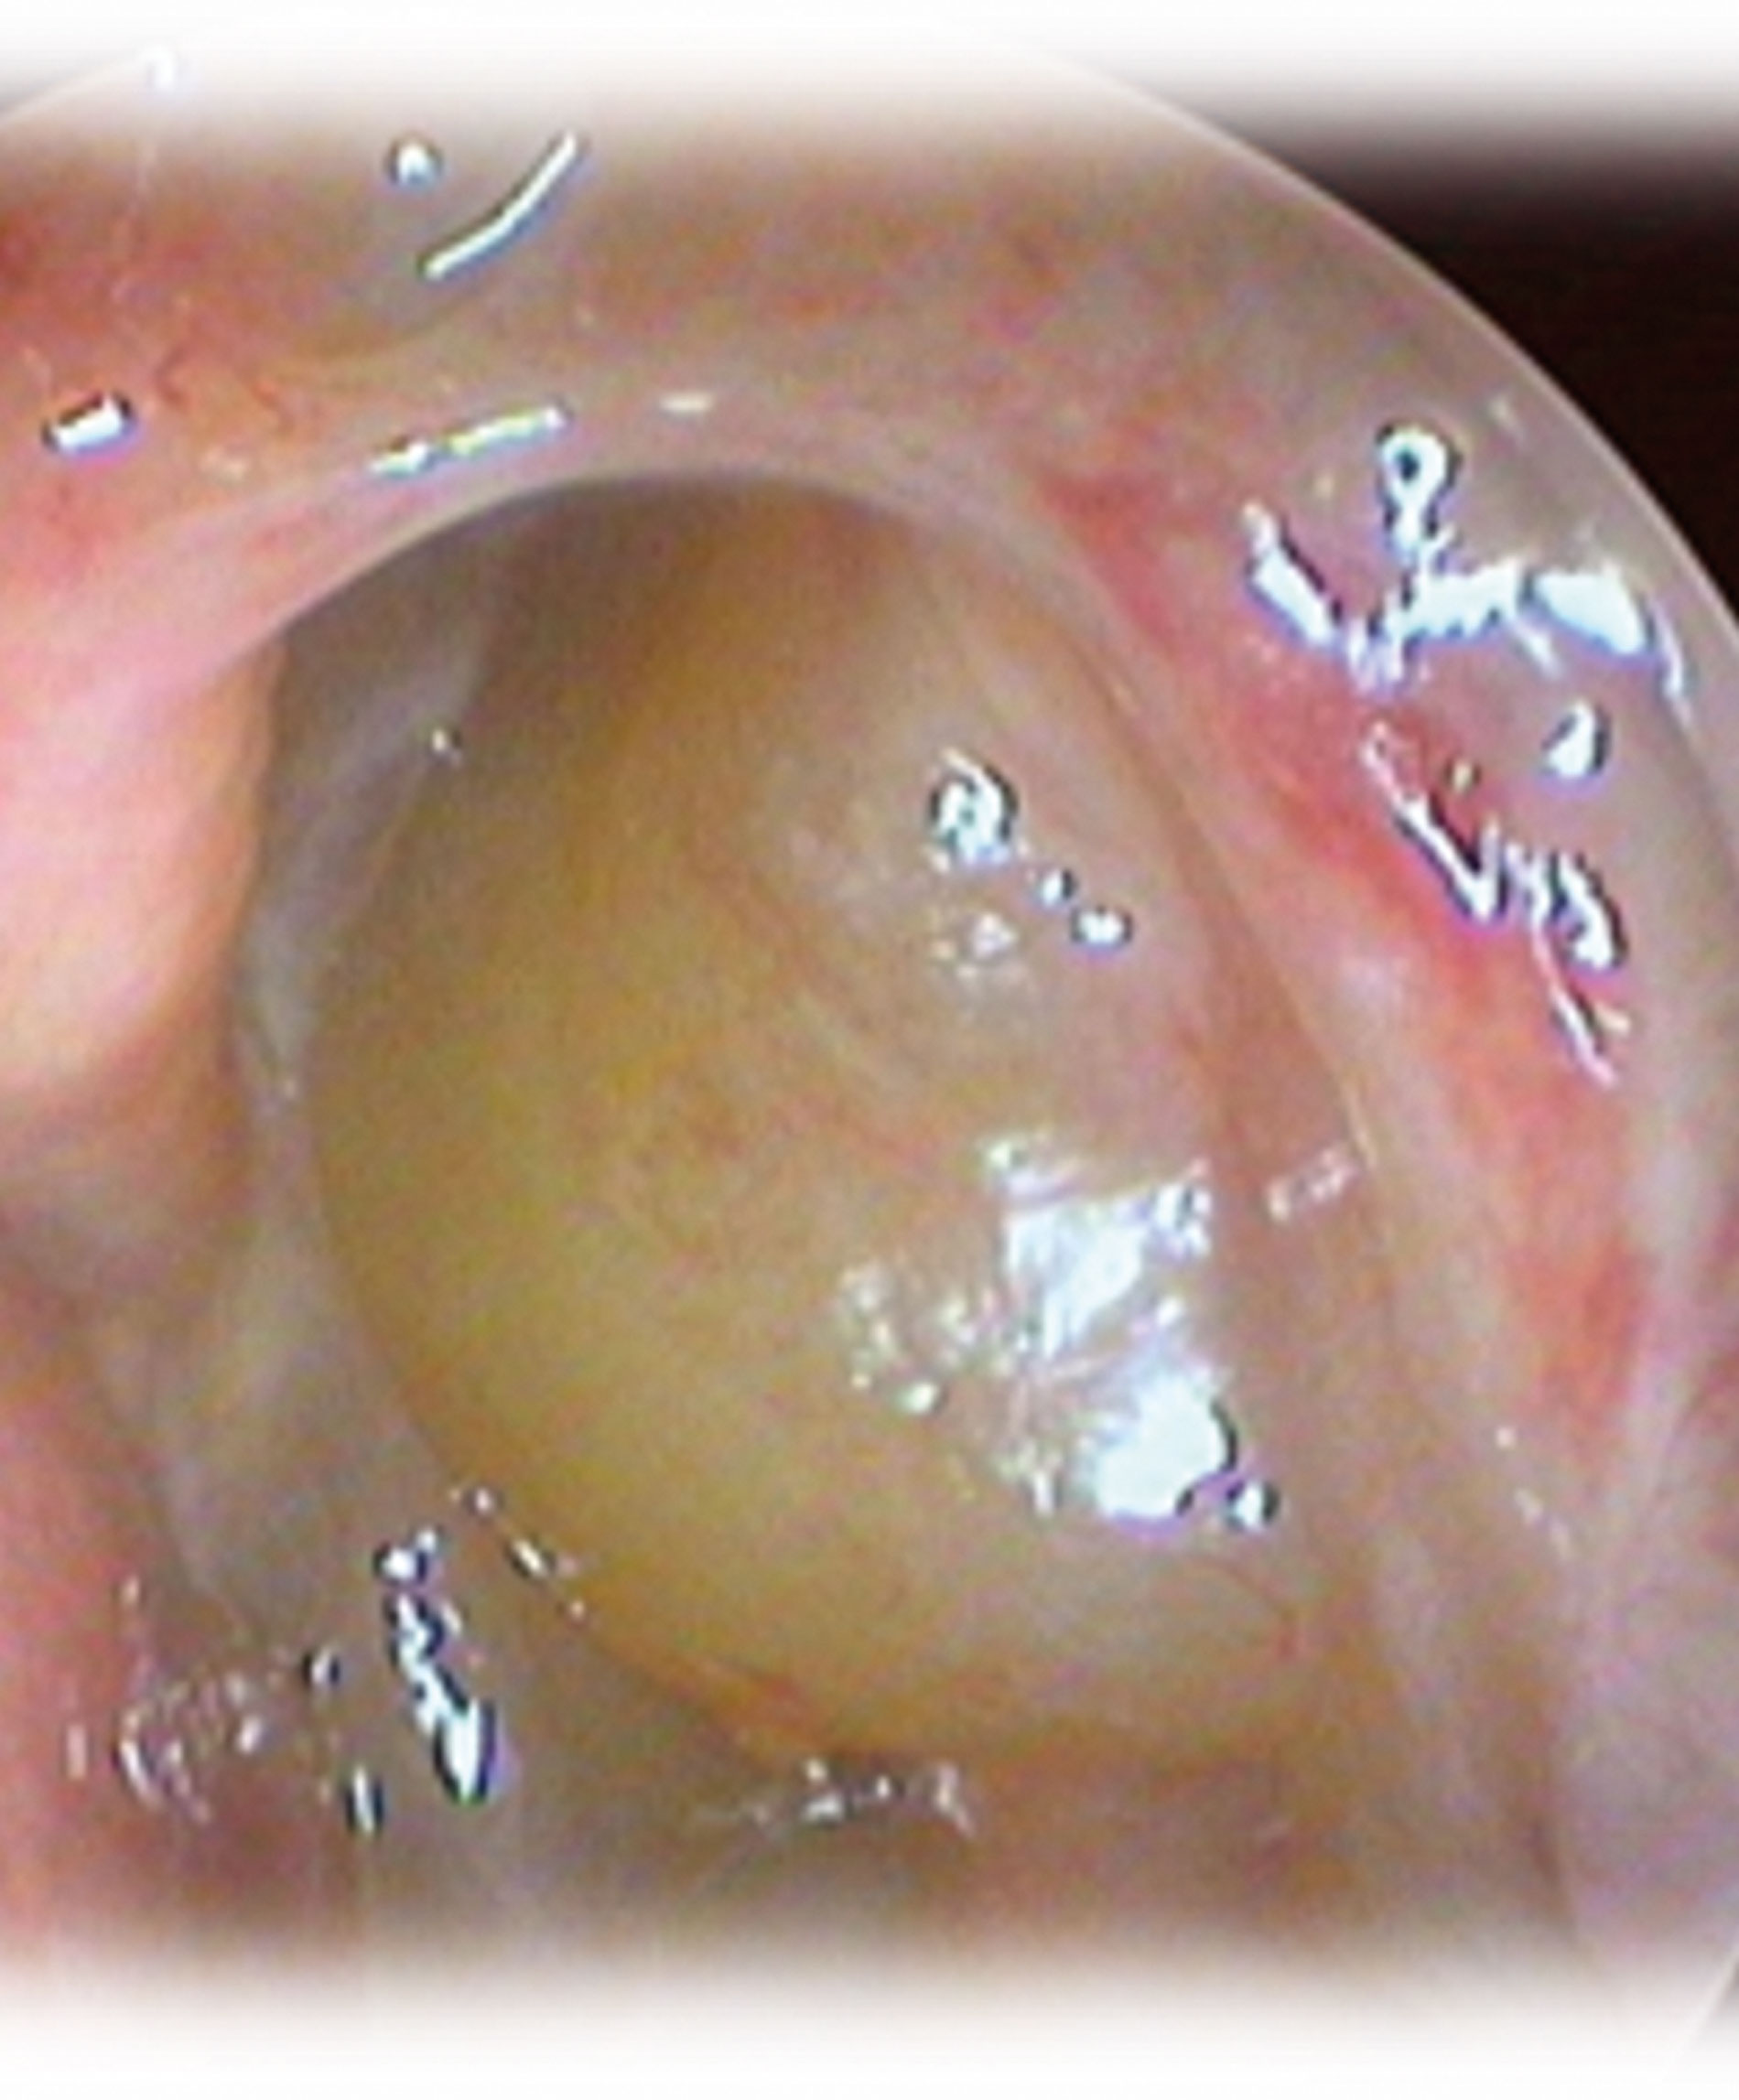

Patients with non-type 2 endotype usually have less asthma and atopy, while type 2 endotype patients often exhibit asthma and/or NSAID-exacerbated respiratory disease and a positive skin prick test or serum IgE levels ≥100 UI/mL. On nasal endoscopy, non-type 2 endotype patients present with purulence, whereas type 2 endotype patients show polyps and eosinophilic mucin.

Non-type 2 endotype manifests itself as non-eosinophilic CRS. Phenotypic examples of the type 2 endotype include eosinophilic CRS, CRS with nasal polyps, allergic fungal rhinosinusitis, and central compartment allergic disease [1,3].